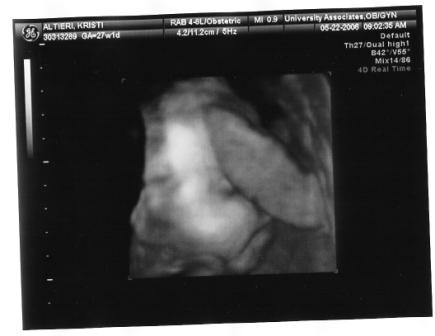

I'm back and everything went great. The cyst is barley visible and the doc said she might not need anything done after she is born. I am so happy I can't even explain. I go back in a month for another sono/check-up. I was surprised that they did a 3d sono I totally didn't expect it. She is pushing up against the placenta so there isn't a clear shot of her face.

here you go!

the first one looks great!! what a cutie. so glad all is going well.